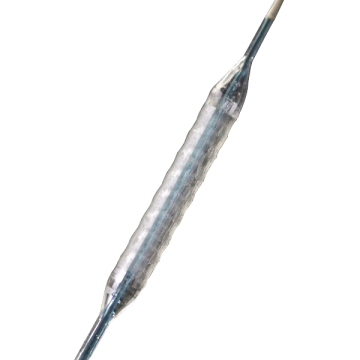

EverFlow® is a Paclitaxel-coated Rapid Exchange PTCA Balloon Catheter with a drug releasing balloon system for the treatment of coronary vessels. EverFlow® is designed to improve the lumen diameter and to reduce restenosis in the treatment of lesions in native coronary arteries.